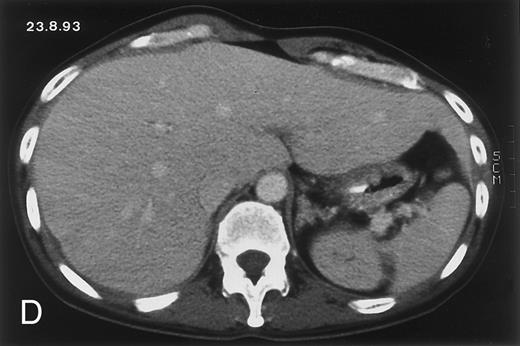

Radiologic evolution in patient A. (A) Postcontrast abdominal CT scan on March 16, 1993 shows multiple small hypodense areas in all segments of the liver, suggestive of hepatic candidiasis. Seven days previously, the patient had recovered from severe neutropenia after the first cycle of chemotherapy for AML. (B) On April 23, 6 days after the neutrophil count had dropped below 500/μL in the second cycle of chemotherapy, there is no evidence of focal lesions on postcontrast CT scan. (C) On June 18, when neutrophils were normalized for 46 days, CT scan again shows multiple small abscesses.

(D) On August 23, 15 days after the neutrophil count had dropped below 500/μL in the third chemotherapy cycle, focal liver lesions clearly decreased in size and number. (E) On September 30, 35 days after neutrophil recovery, multiple hepatic abscesses are seen (arrowhead). To show maximal extent of lesions the scan shown is at a slightly different level. (F) On June 16, 1994, 230 days after neutrophil recovery, the CT scan has normalized.

Evolution of fungal lesions on CT scans during and after neutropenia is summarized in Table 2. Figure 1 (patient A) and Fig 2 (patient B) serve to illustrate Table 2.

In three patients, multiple round lesions were seen on postcontrast CT scans of the abdomen in the liver and the spleen, while in two cases, lesions could only be seen in the liver (Table 2). Following the diagnosis of disseminated candidiasis, these lesions decreased in size and visibility during subsequent neutropenia in three patients (compare Fig 2A and B) and disappeared completely in two patients (compare Fig 1A and B). The numbers of days of severe neutropenia (neutrophils <500/μL) at the time the CT scan was performed are listed in Table 2. After recovery from neutropenia and despite continued antifungal therapy, the size and visibility of the lesions increased again (Fig 1C). Similarly, the number of days since recovery from severe neutropenia (neutrophils >500/μL) are listed in Table 2. In two of three patients treated with another cycle of myeloablative chemotherapy, this waxing and waning pattern of radiologic lesions could be seen again (Fig 1D and E). In all patients, lesions eventually disappeared (Figs 1F and 2D) after prolonged antifungal therapy.